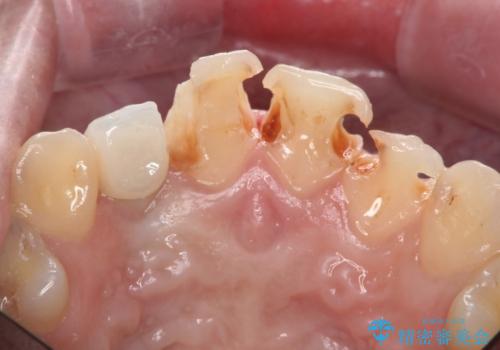

- 虫歯の治療を繰り返した前歯の見た目の改善を求めて来院されました。

大きく詰められたコンポジットレジンと虫歯の再発が見られ、経年劣化により審美性も損なわれていました。

充填されたコンポジットレジン・再発した虫歯を神経に影響が出ないよう丁寧に除去し再充填をしたのちオールセラミッククラウンで前歯の審美性を回復します。

※右上2のインプラント治療は他院のものです。